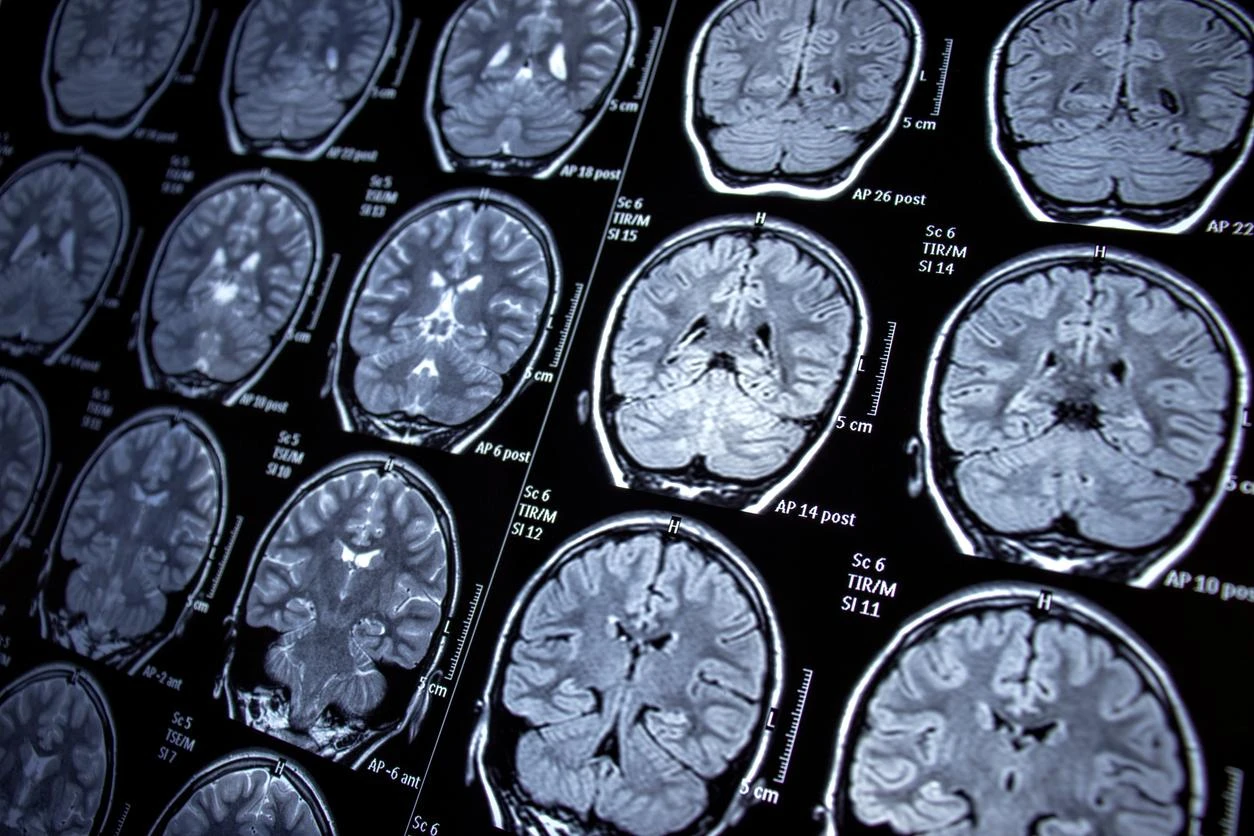

Giới khoa học Trung Quốc đã công bố kế hoạch xây dựng một máy quét não cấp độ khủng khiếp, được đánh giá là mạnh nhất thế giới hiện nay. Máy này có khả năng tích tụ từ trường cực mạnh, giúp lần đầu tiên trong lịch sử dựng lại hoạt động của toàn bộ các neuron thần kinh trong bộ não người đang sống.

Đây là một thiết bị chụp cộng hưởng từ (MRI) mạnh nhất, không chỉ làm tốt những gì công nghệ hiện nay đang làm mà còn cho phép theo dõi các phân tử hóa học trong não như natri, phốt-pho, và kali. Dự án sẽ tiêu tốn hàng tỉ Nhân dân tệ và được dự đoán mang lại "cuộc cách mạng trong lĩnh vực nghiên cứu não bộ".